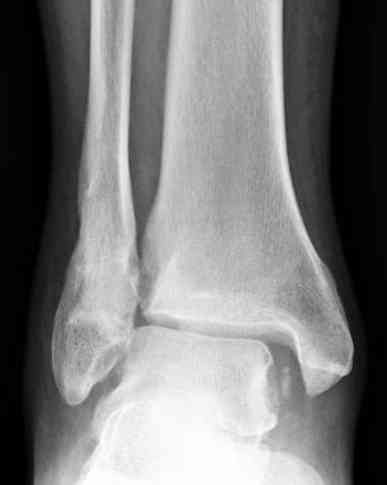

Мне кажется есть все основания попытаться сделать остеосинтез. Боль вследствие нестабильности. Нестабильность вследствие неанатомичного положения дистального отломка малоберцовой кости. Через 1,5 вполне возможно разобщить, репонировать и фиксировать длинный косой перелом наружной лодыжки. Вероятно, одновременно придется делать медиальный доступ для мобилизации внутренней лодыжки. Мы оперируем таких пациентов, функциональные (объем движений) результаты конечно хуже по сравнению с теми кого оперируем в первые 5-10 дней, но вполне удовлетворительные.

Согласен, на предоставленных рентгенограммах все основания для проведения открытого остеосинтеза.

сроки действительно небольшие, но если мы его и возьмем, то пройдет еще минимум неделя, кроме того смущает впечатление сращения н/лодыжки, похоже, что придется не разобщать,а остеотомировать, формирование оссификатов в полости сустава с медиальной стороны, да и сам пациент 1,5 месяца по поводу своей травмы сильно не напрягался